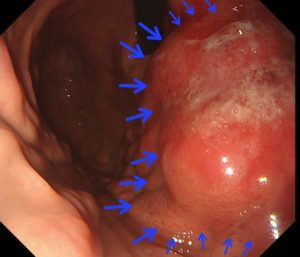

当院の胃内視鏡で見つかった進行胃癌1